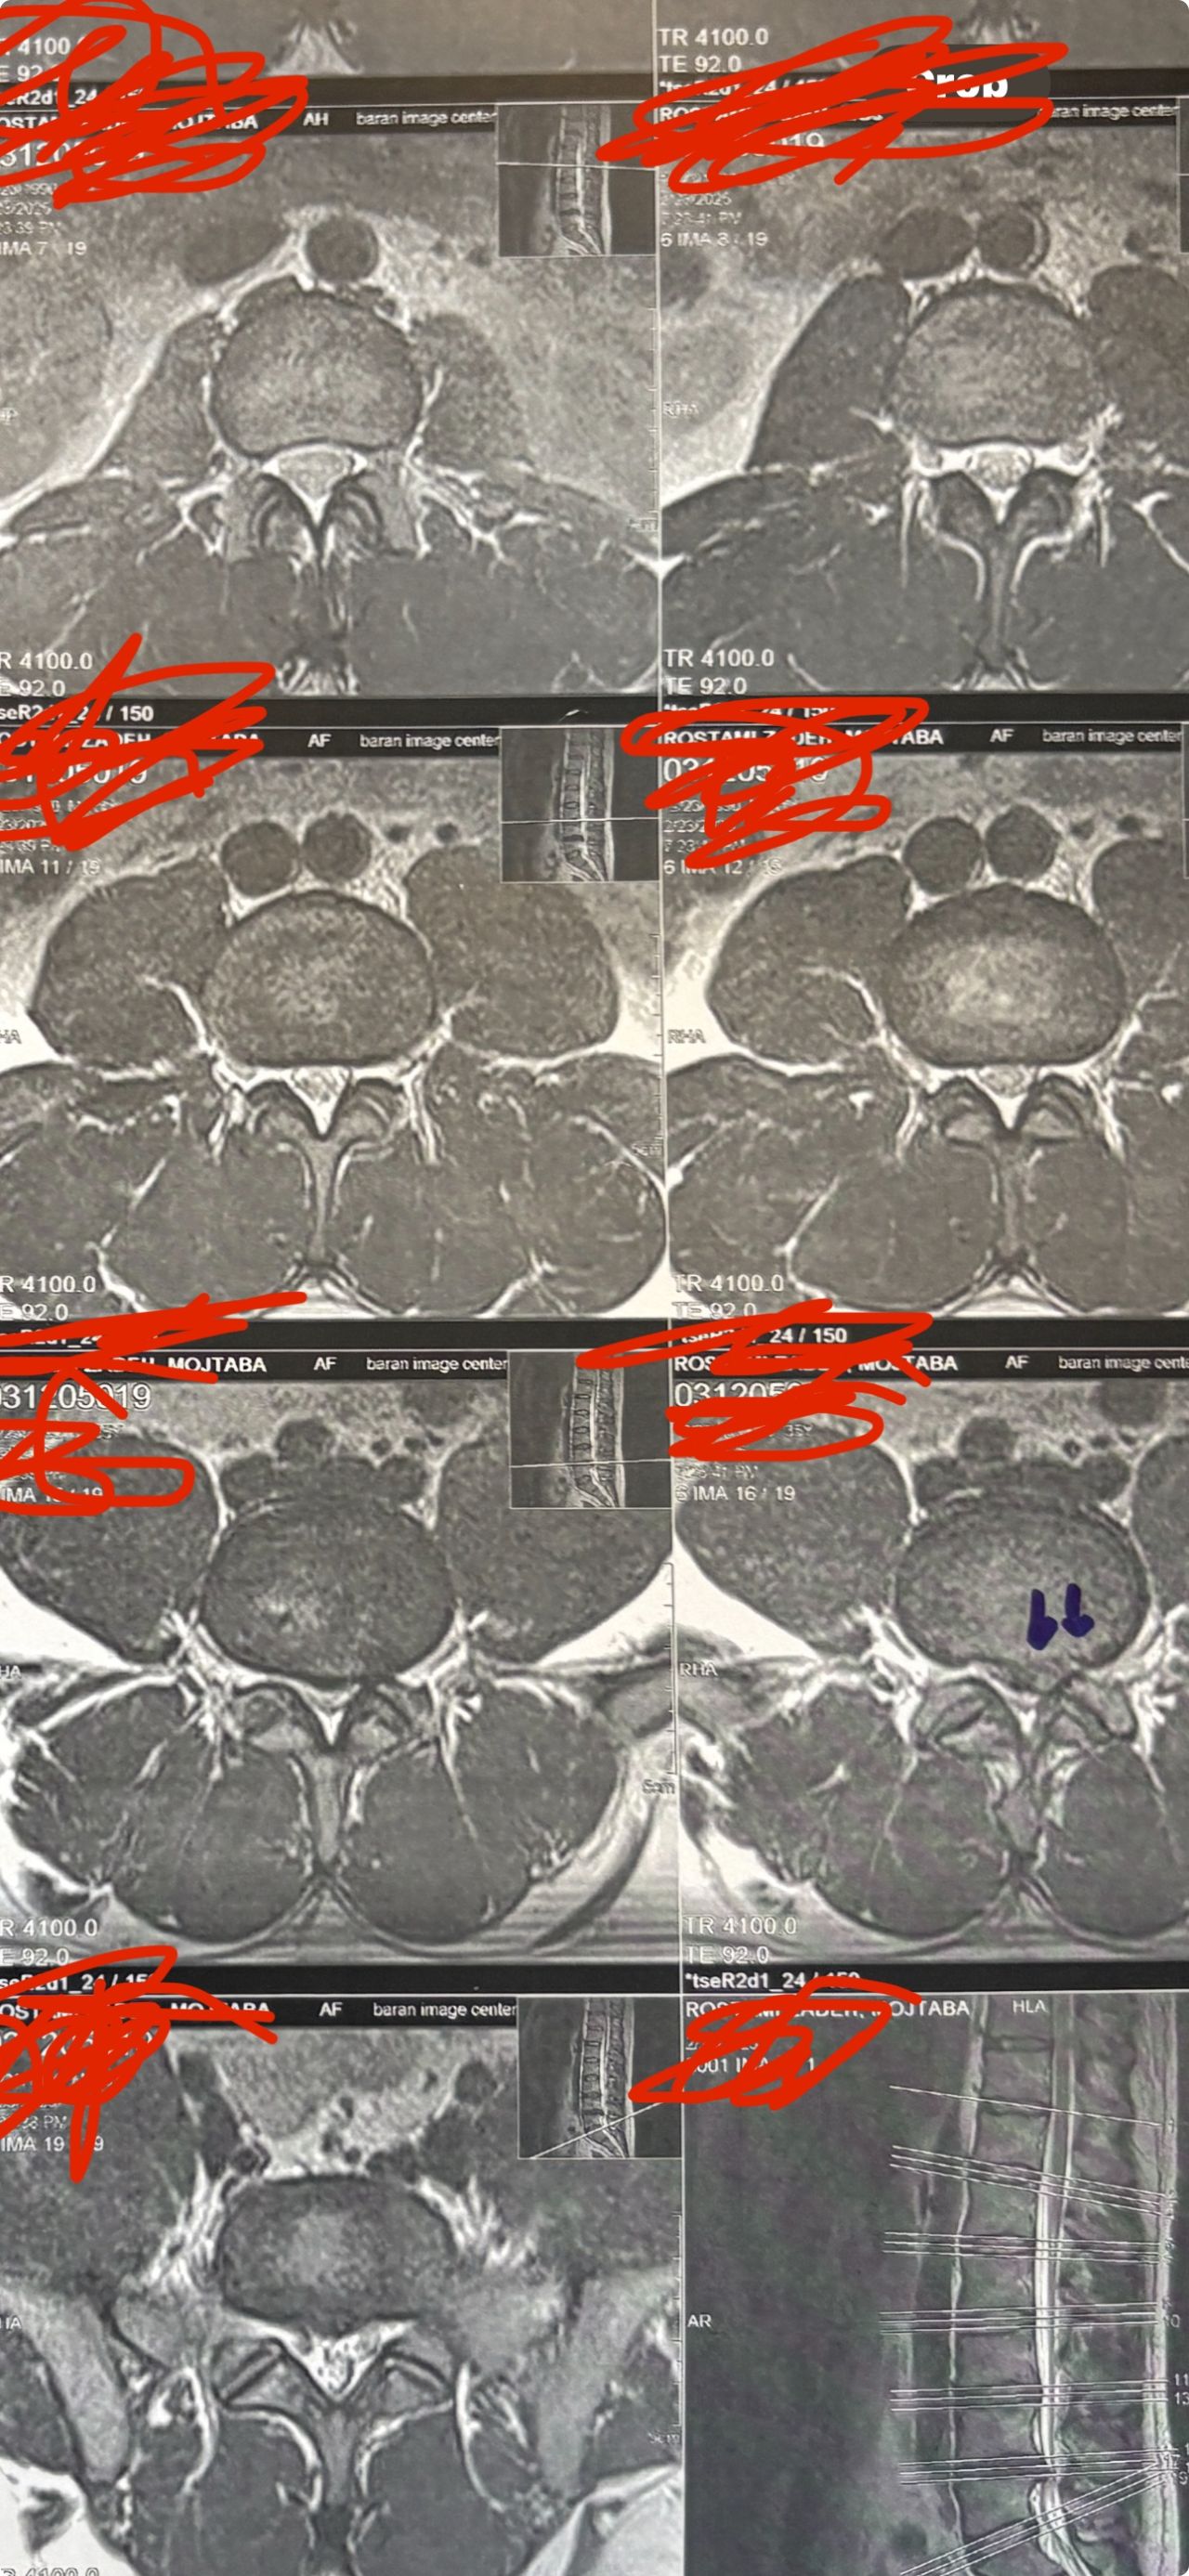

Case 5

46 years old female patient presented to my clinic yesterday june 1/2025 with LBP and radicular L leg pain for several months which hasn’t responded to physio 2 neurosurgeons have visited her and didn’t suggest any surgery Neurological exam was unremarkable please see her mri/ emg/ncv and her huge tarlov cyst and possible L IVF L4-5 hyperbulge I ordered sacrum mri and ct scan and new emg/ncv and asked her with her sacral Ct scan and MRI first sees another two famous neurosurgeons and see if that large cyst is the reason for her pain if not i can work on her L4-S1 area Do you think her radicular pain can originate from her large cyst in sacrum? Do you consider surgery and removing her sacral cyst?